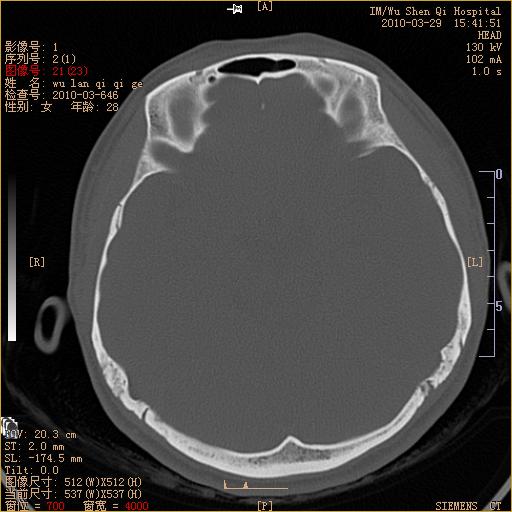

标题: CT25398:女,左耳流脓两年余,带有异物 [打印本页]

标题: CT25398:女,左耳流脓两年余,带有异物

左侧中耳乳突炎,不排除胆脂瘤形成。

左侧中耳乳突炎,胆脂瘤形成。

左侧中耳乳突炎,不排除胆脂瘤形成

1)左侧慢性中耳乳突炎并肉芽肿(或胆脂瘤)形成。2)考虑左侧颞骨慢性炎症伴骨质增生硬化,不排除骨纤。